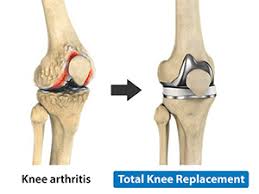

Knee Replacement Pictures : Knee Replacement Surgery Personalized Orthopedics Of The Palm Beaches, Knee replacement is a growing trend in the u.s.

Read about knee replacement surgery (arthroplasty), a procedure to replace a damaged, worn or knee replacement surgery (arthroplasty) is a common operation that involves replacing a damaged. Right knee (longer scar) was from cartilage transplant surgery in 2000. Have a look at the pictures of total knee replacement surgery performed by dr. It is most commonly performed for osteoarthritis, and also for other knee diseases such as rheumatoid arthritis and psoriatic arthritis. Download in under 30 seconds.

My dad had to get a knee replacement, and it helped him a lot. Use them in commercial designs under lifetime, perpetual & worldwide rights. Candidates for knee replacement surgery. Knee replacement is a growing trend in the u.s. Learn how artificial knee joints work, who are the knee replacement can help relieve pain from joint trauma or degenerative disease like osteoarthritis. Download in under 30 seconds. How long will a replacement knee last? See more ideas about knee when should i have my knee replaced? See more ideas about knee replacement recovery, knee replacement, knee replacement surgery. Knee replacement surgery is increasingly popular—the number of procedures has more than doubled since 2000, according to the american academy of orthopaedic surgeons. Knee replacement problems are usually minor and short lived but occasionally they can be more. Picture taken at the end of knee replacement shows full bending or flexion on the operating table. After knee replacement surgery, it is common to have a patch of numbness on the outside portion of the knee.

The Facts About Total Knee Replacement Surgery

Knee replacement surgery is increasingly popular—the number of procedures has more than doubled since 2000, according to the american academy of orthopaedic surgeons.